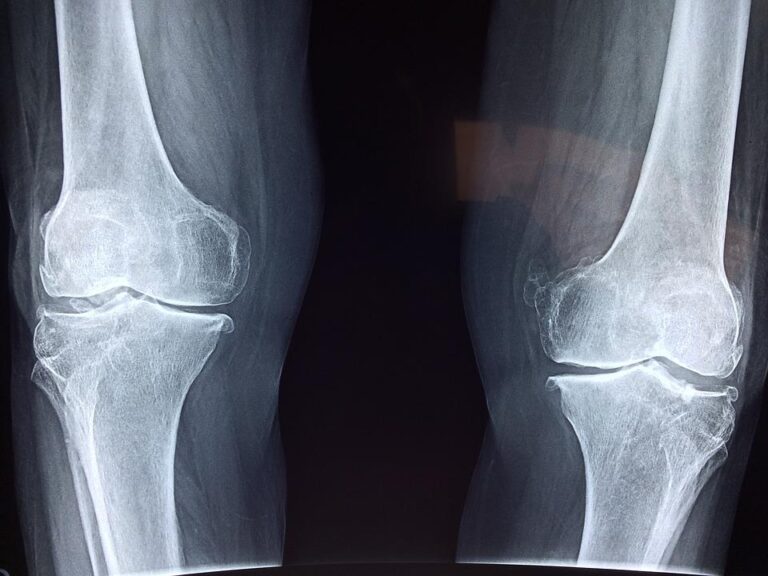

Téměř 13 procent osob trpí kloubními obtížemi

Podle Ústavu zdravotnických informací a statistiky ČR je počet osob, které v roce 2021 vešly do kontaktu se zdravotním systémem z důvodu kloubních obtíží různého charakteru na pozici hlavní diagnózy, celkem 1 354 477 milionu. Oproti roku 2020 vzrostl počet o 32 907 osob. Jedná se o téměř 13 % celkové populace ČR. V posledních […]

Když se lámou kosti

Mírný pád, lehký náraz nebo pouhé kýchnutí. Situace, které mohou skončit zlomeninou, a překvapivě tak odhalit nemoc, která se nenápadně vyvíjí celá léta. Kosti člověka trpícího osteoporózou jsou křehké, snadněji se lámou, a právě fraktura bývá často prvním příznakem tohoto onemocnění. Vyskytuje se u každé třetí ženy a jednoho z pěti mužů nad padesát let. […]